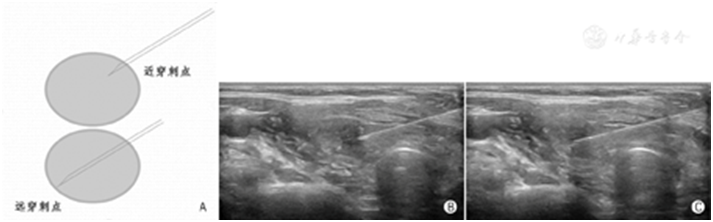

在目标结节内针尖须作较大幅度来回提插移动,最理想的幅度是从目标结节的近穿刺点达其远穿刺点(图16),以获取穿刺针道上最大量的标本。

图16贯穿目标结节的大幅度穿刺 A:近穿刺点和远穿刺点示意图;B:近穿刺点声像图;C:远穿刺点声像图